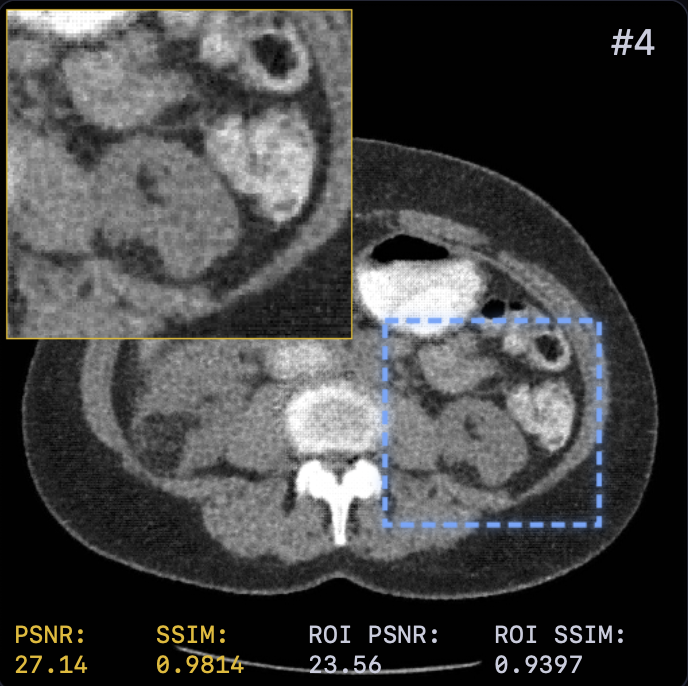

The reconstruction results are shown in Fig. 2. A zoomed-in region was extracted for a closer look with both PSNR and SSIM values attached. LTV preserves fine structures, such as vessel continuity, and reduces streak artifacts—critical for diagnostics—while avoiding the over-smoothing of TV or the anatomical inconsistencies of FBP+U-Net.